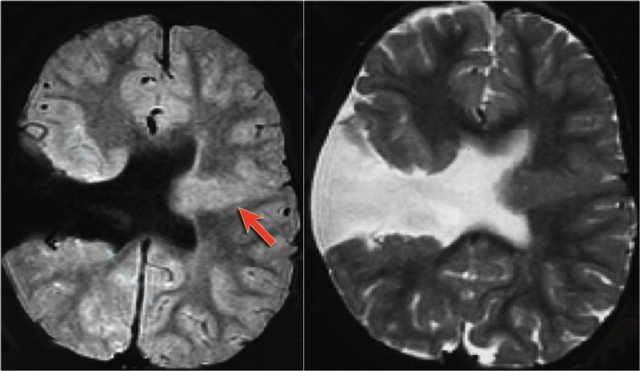

The imaging findings in status epilepticus can mimick mesotemporal sclerosis.

In status epilepticus a hyperintense hippocampus can be seen, but there is swelling and no atrophy.

Axial FLAIR, axial DWI and coronal T2WI demonstrate a hyperintense hippocampus with a slightly compressed temporal horn of the lateral ventricle consistent with hippocampal edema.

DWI shows diffusion restriction due to cytotoxic edema in the acute stage of the status epilepticus.

DNET mimicking mesial temporal sclerosis

Axial T2WI shows hyperintense, but enlarged hippocampus with a bubbly appearance.

This is typical for a DNET or dysembryoplastic neuroepithelial tumor, which we will discuss in a moment.

The coronal contrast-enhanced T1WI shows an enlarged hippocampus without uptake of contrast medium.